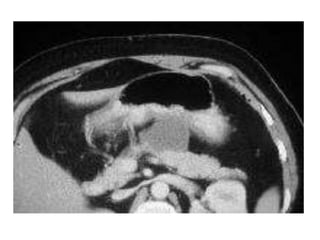

•CT Abdomen with contrast:- phlegmon(inflammatory mass),

CT:

typical findings:

-focal or diffuse parenchymal enlargement

-calcifications may be seen within the parenchyma

-changes in density because of oedema

-indistinct pancreatic margins owing to inflammation

-surrounding retroperitoneal fat stranding

liquefactive necrosis of pancreatic parenchyma: lack of

parenchymal enhancement

infected necrosis

abscess formation : circumscribed fluid collection, little or no

necrotic tissues

haemorrhage: high-attenuation fluid in the retroperitoneum or

peripancreatic tissues